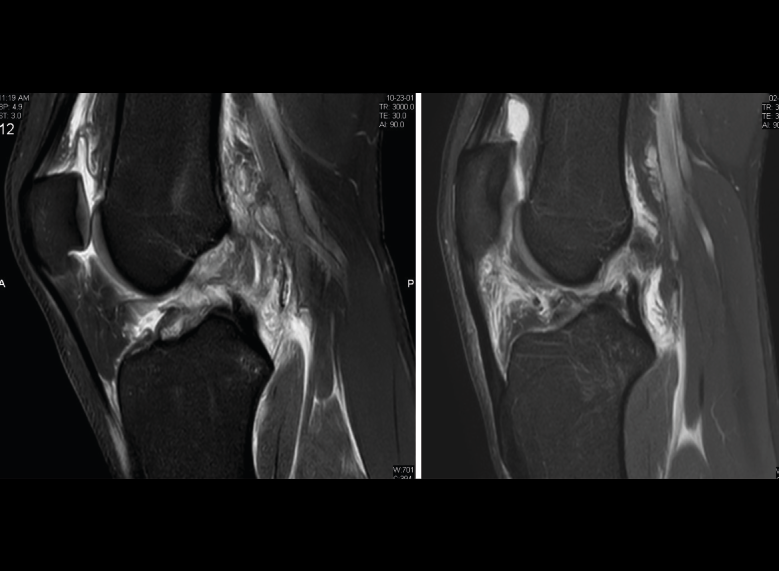

1.2.2. Ligamento cruzado anterior (LCA) (Figuras 40, 41, 42, 43 y 44)

Figura 40. Corte de secuencia sagital T2 Fat-Sat de resonancia magnética de rodilla: ligamento cruzado anterior normal.

Figura 41. Cortes de secuencia sagital T2 Fat-Sat de resonancia magnética de rodilla: rotura central del ligamento cruzado anterior.

Figura 42. Cortes de secuencia sagital T2 Fat-Sat: rotura proximal del ligamento cruzado anterior.

Figura 43. Corte sagital oblicuo T2 de resonancia magnética de rodilla: plastia del ligamento cruzado anterior íntegra.

Figura 44. Corte de secuencia sagital T2 Fat-Sat y T2 de resonancia magnética de rodilla: rotura de plastia del LCA.